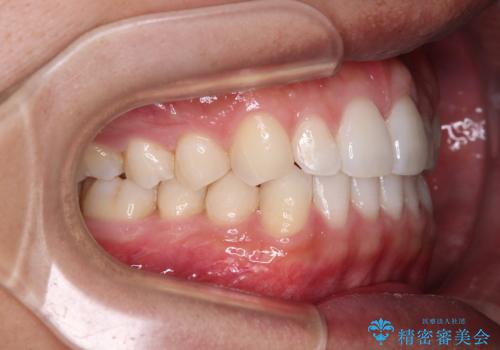

前歯のデコボコとクロスバイト インビザライン矯正治療

- 前歯のデコボコとクロスバイトを治したいとのことで来院された患者様です。

上下顎ともに歯列全体の側方拡大を行い、下顎前歯はIPR(歯と歯の間を削る)によってデコボコとクロスバイトが解消するように設計し、インビザラインにより治療を行うこととしました。

2年弱で終了する予定でしたが、途中来院されなかった時期があり、その後舌側転位している前歯を動かせるところまで動かしたいとのことで4年ほど治療を継続されました。